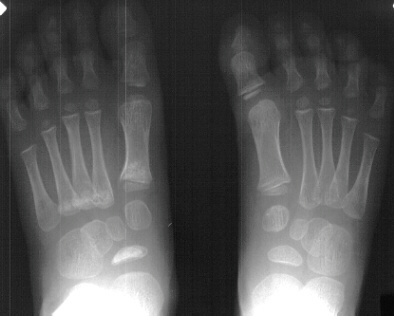

Radiographs of the patient were obtained on her presentation to our clinic. These confirmed the finding of increased radiodensity of the navicular with a flattened appearance to the ossific nucleus. Furthermore they revealed increased density and callus formation in the proximal 1st through 4th metatarsals. This was consistent with multiple non-displaced fractures of the proximal metatarsals secondary to trauma. While Kohler's disease cannot be ruled out in this case, it is more likely that the patient had symptoms produced by her metatarsal fractures. The radiographic appearance of the tarsal navicular almost certainly preceded the acute traumatic event. Therefore, she probably had metatarsal fractures superimposed on irregular ossification of the tarsal navicular giving a clinical picture similar to Kohler's disease.